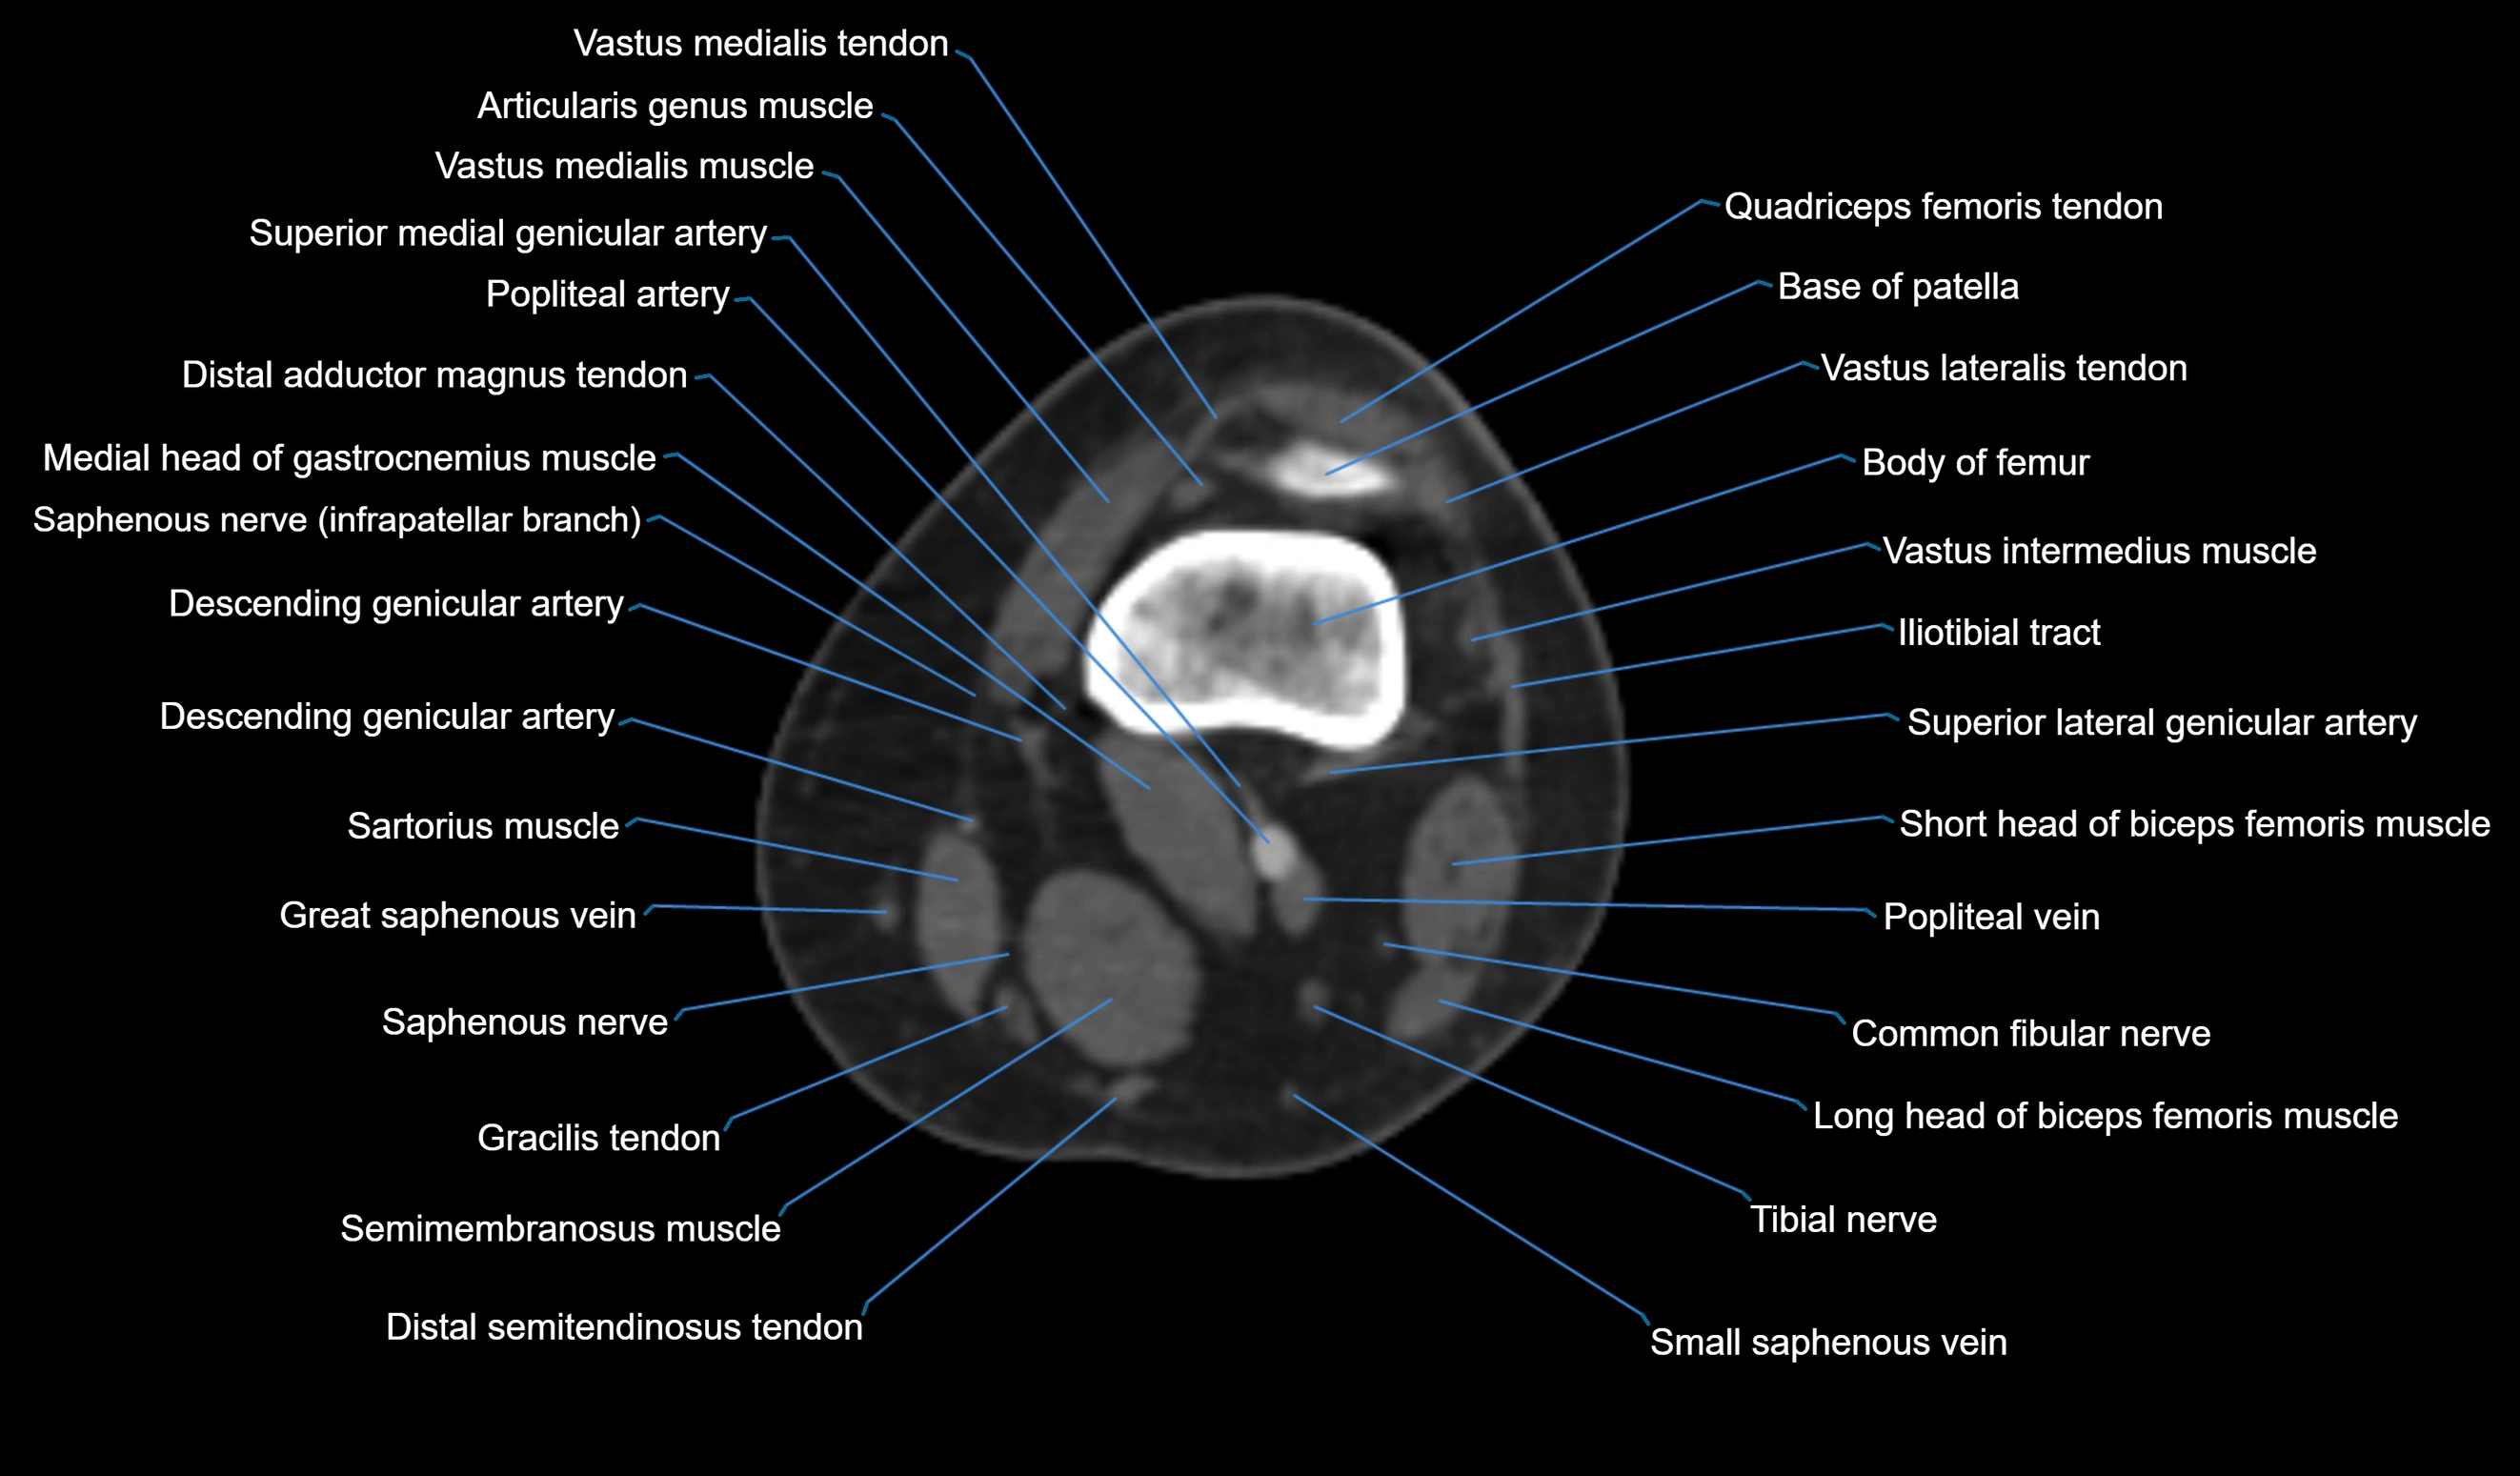

- Base of patella

- Body of femur

- Common fibular nerve

- Descending genicular artery (Articular branches)

- Descending genicular artery (Saphenous branch)

- Distal adductor magnus tendon

- Distal quadriceps femoris tendon

- Distal vastus lateralis tendon

- Distal vastus medialis tendon

- Gracilis Tendon (Proximal)

- Gracilis tendon (Distal)

- Lateral head of gastrocnemius muscle

- Medial head of gastrocnemius muscle

- Popliteal artery

- Popliteal vein

- Saphenous nerve

- Sartorius muscle

- Semimembranosus muscle

- Small saphenous vein

- Superior lateral genicular artery

- Superior medial genicular artery

- Tibial nerve

- Vastus medialis muscle